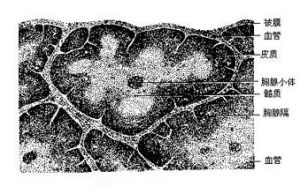

血胸腺屏障,介於血液與胸腺之間。胸腺是一個中樞淋巴器官,能產生多種激素,培養形成淋巴細胞,參與人體免疫活動。通俗點講,胸腺是人體內的軍工廠,擔負著培養共和國衛士的重任,這樣的地方自然不能有外因干擾。該屏障可防止血液中的大分子物質、抗原等進入胸腺皮質,有利於胸腺生產合格的武器。

基本概念 發展情況 生理特徵 醫學研究 生存條件皮質的毛細血管內皮細胞連線緊密,與網狀細胞共同形成血液-胸腺屏障,使循環中的抗原物質不能進入胸腺。血液-胸腺屏障是體內為數不多的幾個生理屏障之一...組成,主要組成部分是淋巴組織。中樞免疫器官包括胸腺和骨髓(在禽類是法布里...